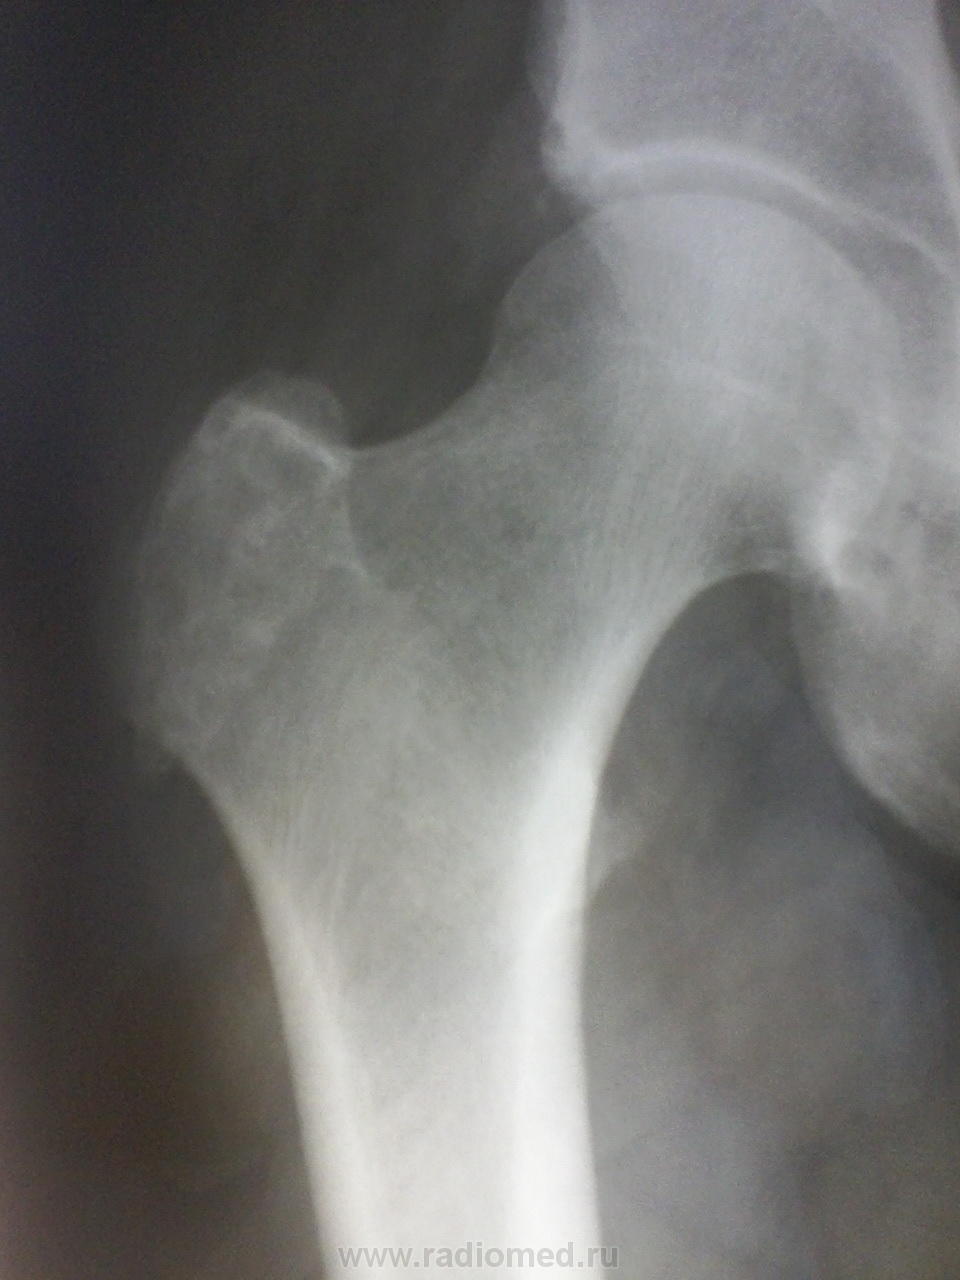

Я бы предположил хондрому, рекомендована КТ тазбедренного сустава, для уточнения характера изменений( даже если предположить, что имеет место образование кости, если честно, не вижу признаков злокачественности).

написала хондрому, контроль через полгода (, думаете надо было КТ рекомендовать ?

Для начала - так хотя бы с отведением снимок...а то вдруг там и "хондромы" то никакой не окажется)))))

Согласен, может, и не оказаться. И если бы не крыша вертлужной... К ней глаз цепляется. Какая-то она обкусанная для такого возраста. Если болит, отправил бы на дообследование. Пусть и её тоже смотрящий там поглядит!)

Намекаете на хондрому?.. А как Вам верхне-наружный отдел вертлужной впадины - может, и он ей задет?..

а сколько средних лет мужчине? опухоль хрящева,я на сколько выдно по снимку, скорее всего хондросаркома

Ну, есть обызвествления мягких тканей.

Я бы написал остеосклероз большого вертела.. и ктшка

Не помню точно, 50-55